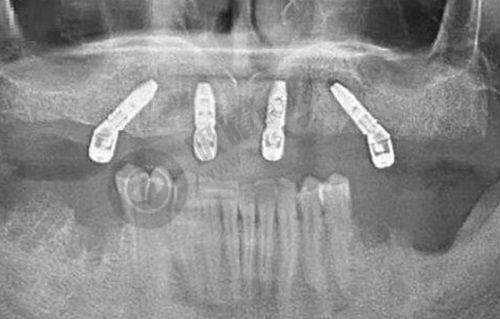

该门诊汇聚了一批具有丰富治疗口腔疾病经验的医生。他们在口腔领域深耕多年,掌握了精良的治疗技术和方法。研究的“瑞士ITI种植”“牙齿美学种植”“牙齿种植”“拔牙”“烤瓷牙”“牙齿矫正”等项目,可以解决患者的口腔疾病治疗难题,能治疗牙颌畸形、牙列不齐、牙体缺损等问题。

门诊的诊疗环境幽雅,拥有精品的硬件配置。精良的口腔诊疗设备,能够为医生的诊断和治疗提供正确的数据支持,提高治疗的精细度和成效。以专科治疗为特色的医疗体系,为客人提供高品质的口腔诊疗服务。